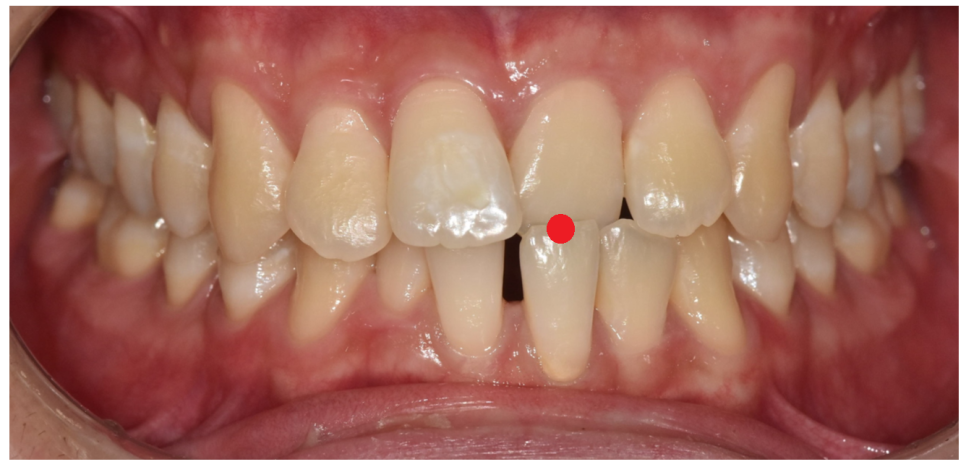

250307 위 아래 앞니가 뒤바뀐 부위

치아 들어가고 나오고를 일정하게 맞춰달라는

말씀을 해주셨어요.

앞니 물림이 뒤바뀐 부분을

"해소"해달라고 하셨습니다.

아래쪽 앞니가 앞으로 나와

치아가 튀어나와 보이는 느낌이라고 하시면서 말이죠.

#21 (왼쪽 윗앞니)이 아랫니보다 안쪽으로 물리고 있어서

전치부 반대교합(Anterior Crossbite) 상태

아래 앞니(#31, #41)는 공간이 벌어져 있으면서

앞으로 나와 있는 모습이었습니다.

쉽게 말하면 위 아래 치아가 거꾸로 물리는데...

일부 치아만 반대로 물리는 상황

이런 것을 부분적 반대교합이라 말합니다.